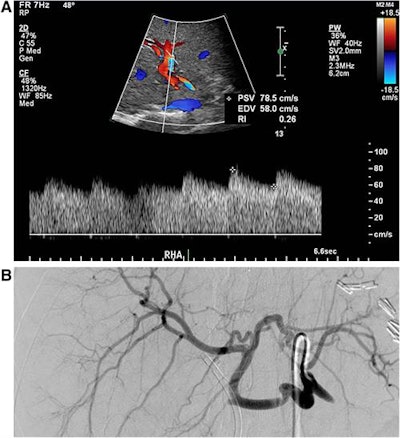

Transplant hepatic arterial patency is typically evaluated via spectral Doppler ultrasound using both qualitative analysis and quantitative measurements, including the pulsatility index and the most commonly used method of resistive index for assessing blood flow downstream from the stenosis. However, these quantitative metrics are calculated using only one or two points in the spectral Doppler waveforms, according to Chan.

To help, the group developed a technique that uses all points of the waveform to quantitatively detect stenosis, calculated via a stenosis index. They then performed a retrospective study to test their hypothesis that the stenosis index would be more sensitive and specific than the resistive index and pulsatility index for identifying patients with hemodynamically significant transplant hepatic artery stenosis that required intervention (J Ultrasound Med, April 2017, Vol. 36:4, pp. 809-819).

The stenosis index was then calculated from each patient's spectral Doppler ultrasound images by obtaining the ratio of the area under the high-frequency signal to the low-frequency index signal in the spectral Doppler. After also calculating the resistive index and pulsatility index, the researchers compared the accuracy of all three metrics using receiver operating characteristic (ROC) analysis.

Of the 69 patients, 48 were determined on angiography to have transplant hepatic arterial stenosis requiring intervention; the remaining 21 had no evidence of stenosis on angiography. The researchers found that the stenosis index was lower in patients with transplant hepatic arterial stenosis (1.04 ± 0.20) than in those without stenosis (1.39 ± 0.30). The difference was statistically significant (p < 0.001).